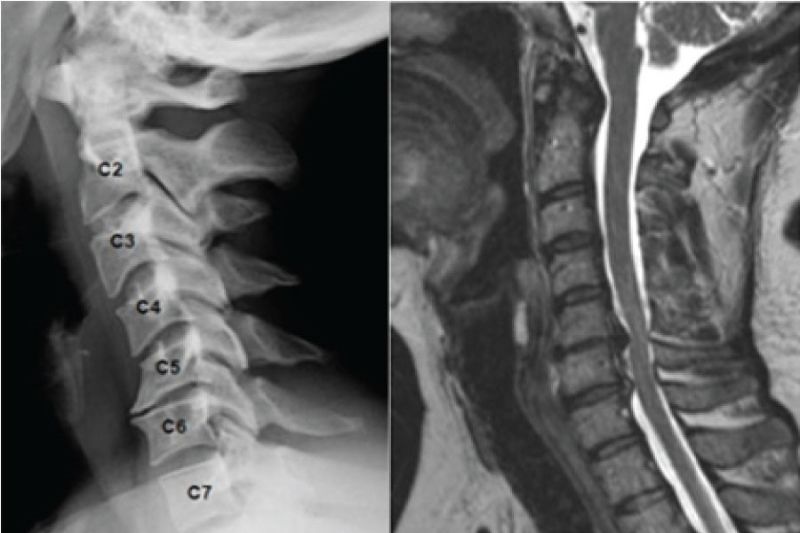

Cột sống cổ gồm 7 đốt sống, được ký hiệu từ C1 đến C7. Giữa các đốt sống là hệ thống đĩa đệm đóng vai trò như “tấm đệm giảm xóc”, giúp cột sống vận động linh hoạt và hấp thụ lực. Khi đĩa đệm bị thoái hóa, mất nước hoặc chịu áp lực kéo dài, nguy cơ thoát vị sẽ tăng lên rõ rệt.

MRI là phương pháp chẩn đoán quan trọng và chính xác nhất hiện nay đối với thoát vị đĩa đệm cột sống cổ. Hình ảnh MRI cho phép bác sĩ quan sát rõ cấu trúc đĩa đệm, vị trí nhân nhầy thoát ra, mức độ chèn ép rễ thần kinh hoặc tủy sống, cũng như tình trạng dây chằng và mô mềm xung quanh.

Kết quả chụp MRI có giá trị quan trọng trong chẩn đoán thoát vị đĩa đệm cột sống cổ

Chụp X-quang cột sống cổ

X-quang giúp đánh giá tổng thể cấu trúc cột sống cổ, phát hiện các bất thường như cong vẹo, mất đường cong sinh lý, hẹp khe gian đốt sống hoặc gai xương do thoái hóa. Tuy không thấy trực tiếp khối thoát vị, X-quang vẫn có giá trị hỗ trợ chẩn đoán và loại trừ các nguyên nhân khác gây đau cổ.